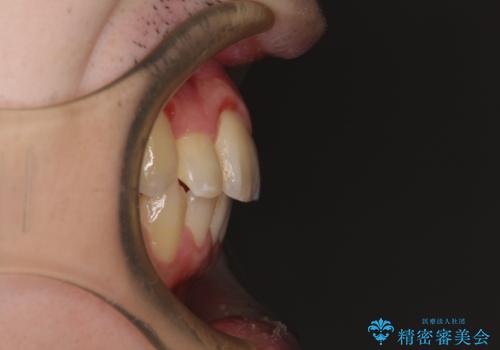

前歯のクロスバイトや八重歯の他に、左右最後臼歯のシザーズバイト(鋏状咬合)が認められました。

シザーズバイトは強く咬合する奥歯を移動させるため、多くの場合においてワイヤー矯正の装置のみでは改善が困難となります。

奥歯の咬み合わせ改善は治療初期からしっかりとアプローチする必要があるため、補助装置を積極的に利用します。